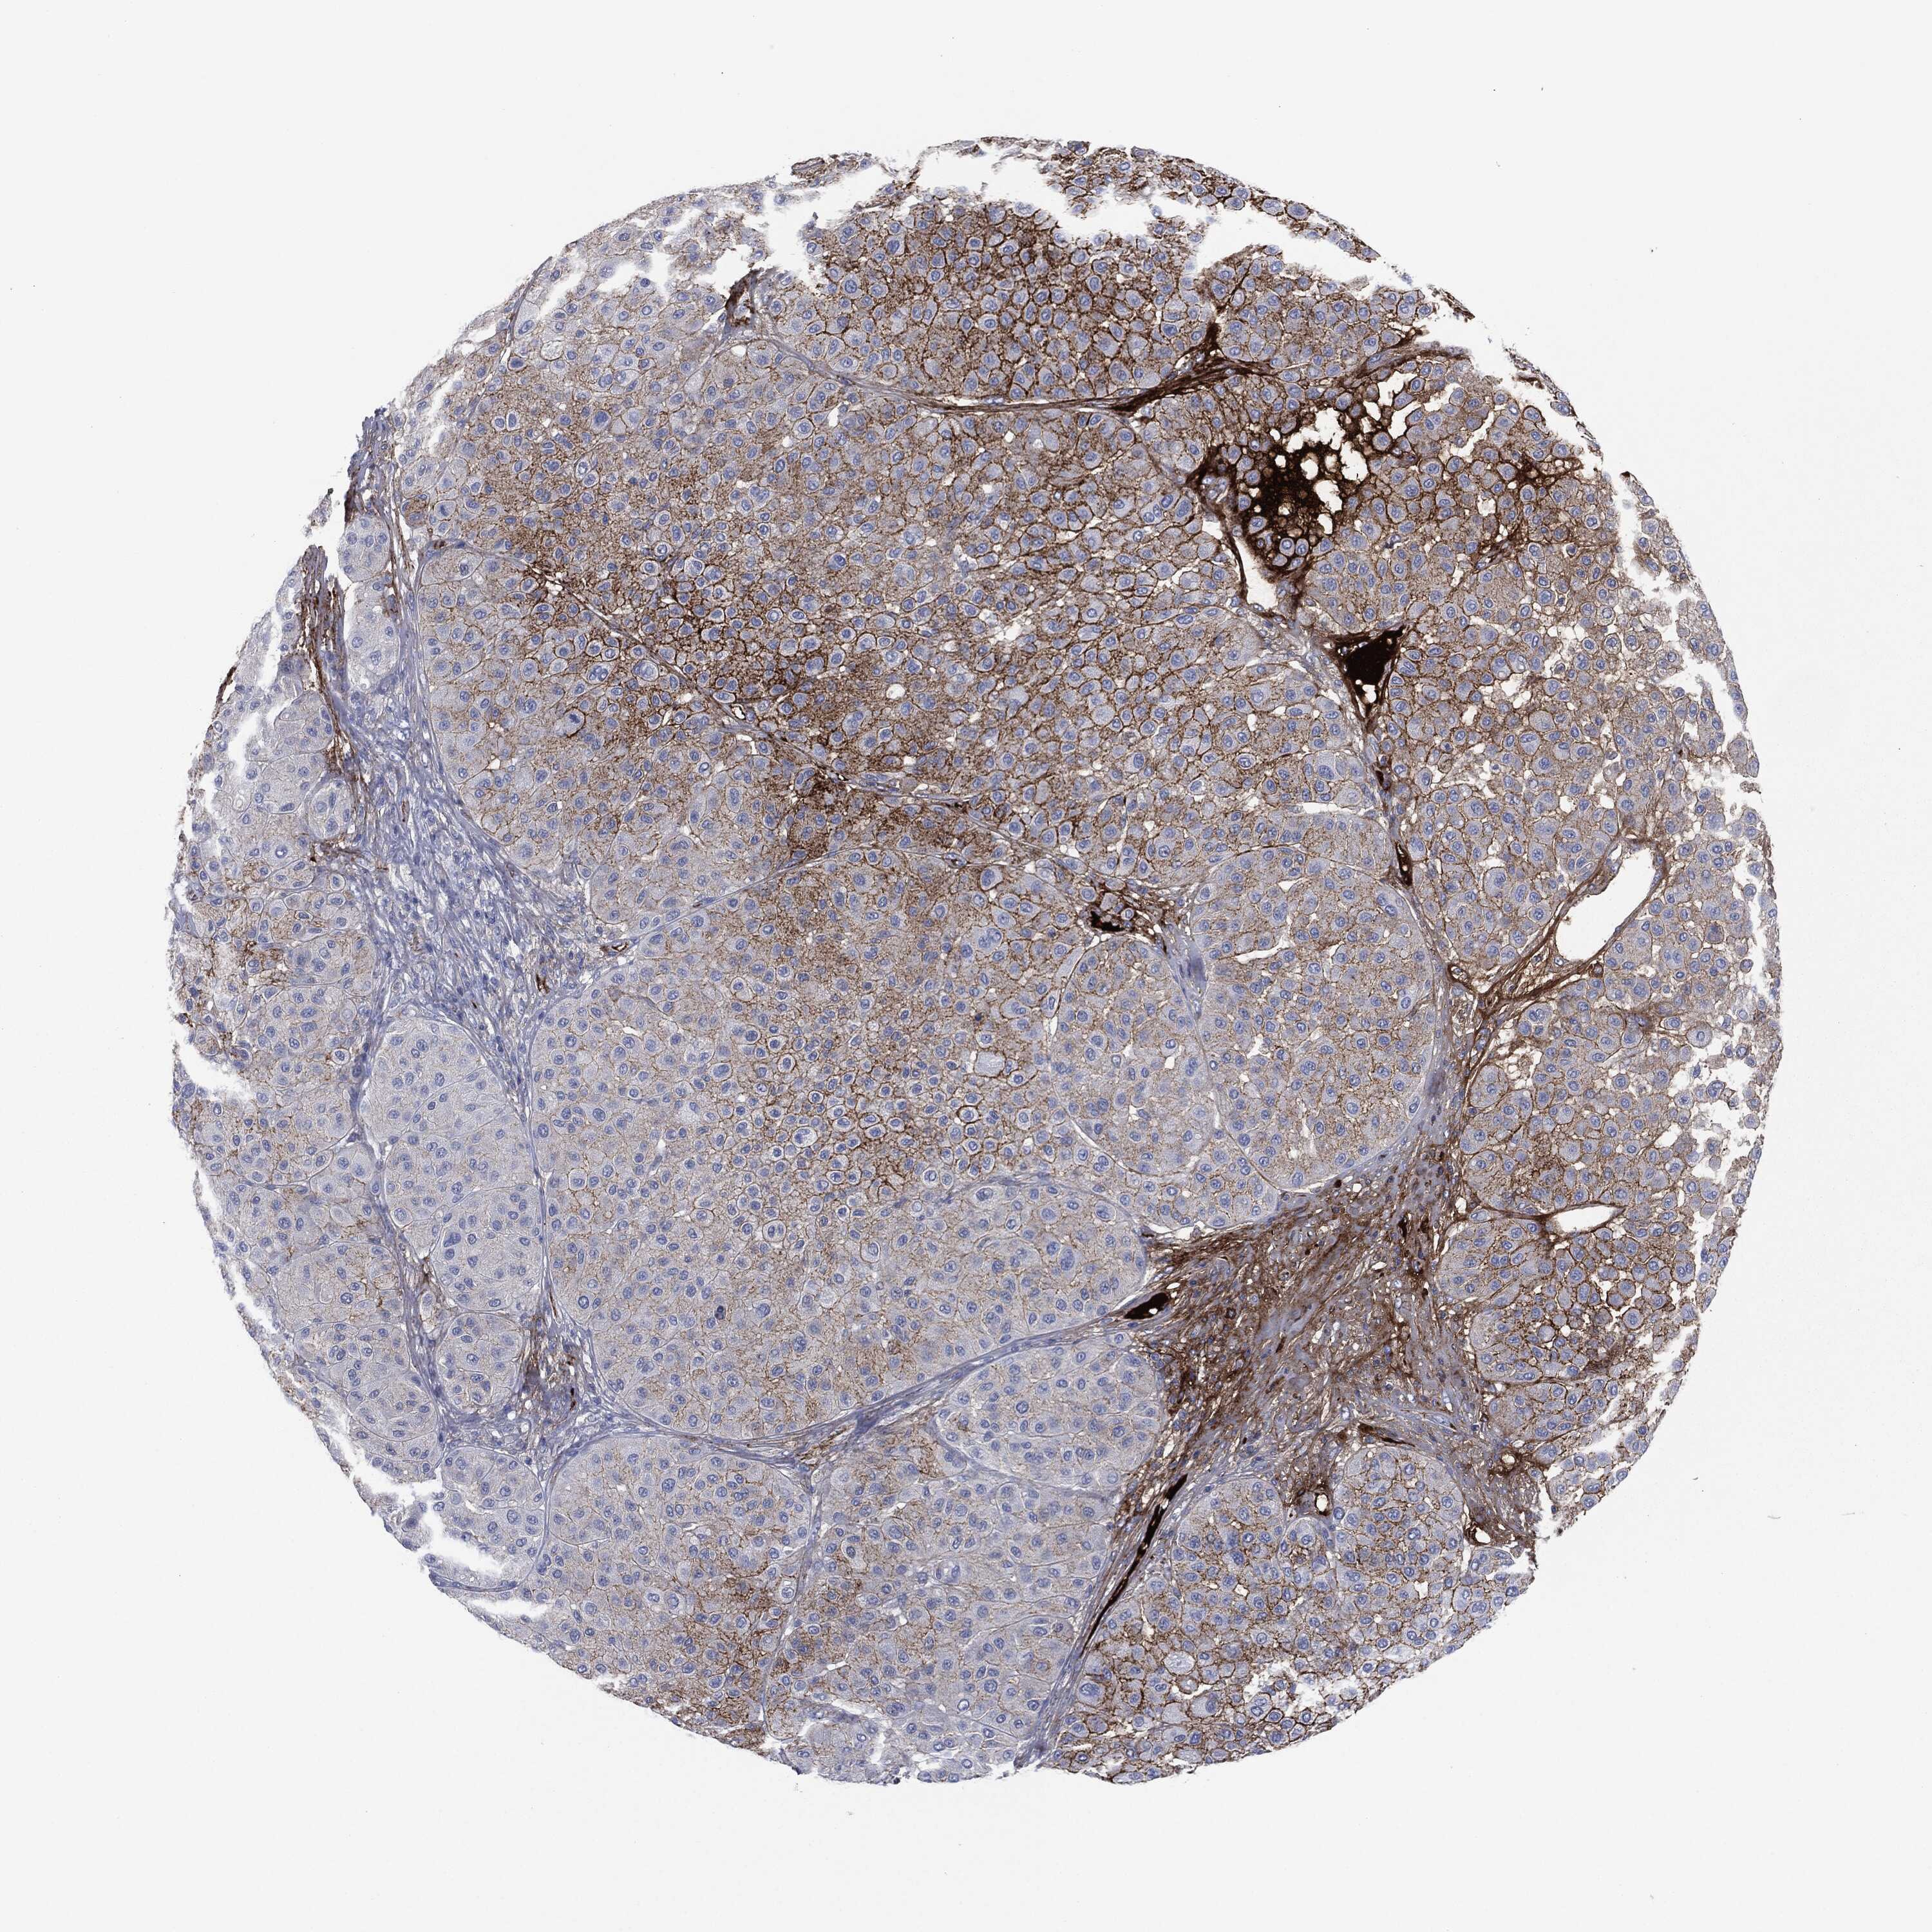

MELANOMA - Protein expressioni

A mouse-over function shows sample information and annotation data. Click on an image to view it in a full screen mode. Samples can be filtered based on level of antibody staining by selecting one or several of the following categories: high, medium, low and not detected. The assay and annotation is described here.

Note that samples used for immunohistochemistry by the Human Protein Atlas do not correspond to samples in the TCGA dataset.

Antibody stainingi

Antibody staining in the annotated cell types in the current human tissue is reported as not detected, low, medium, or high, based on conventional immunohistochemistry profiling in selected tissues. This score is based on the combination of the staining intensity and fraction of stained cells.

Each image is clickable and will lead to virtual microscopy that enables deeper exploration of all samples and also displays staining intensity scores, fraction scores and subcellular localization as well as patient and tissue information for each sample.

HPA049793

CAB016070

CAB080297

CAB080298

CAB080299

Malignant melanoma, NOS

Malignant melanoma, Metastatic site